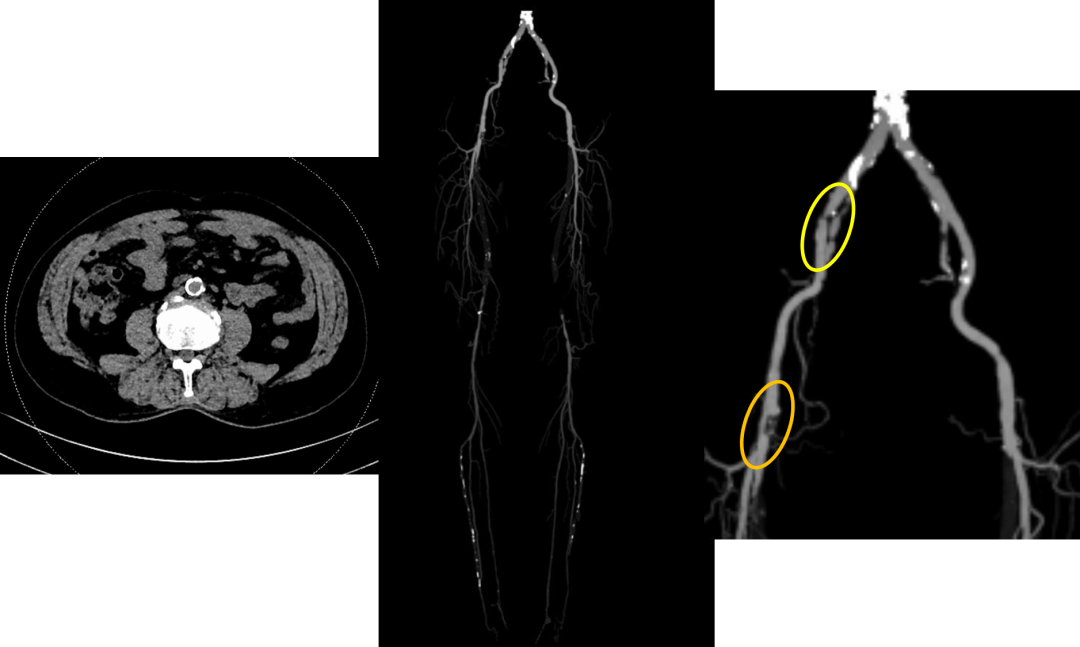

男性,67岁

右下肢间歇性跛行3年,右足溃疡3月

既往:颈动脉狭窄、十二指肠溃疡、COPD

有吸烟史50 多年,40支/天,戒烟3年

Wound, Ischemia, and foot Infection (WIfI) Stage 3: W1I3fI1

Global Limb Anatomic Staging System (GLASS) Stage III

Femoropopliteal Grade 4: (Total length SFA occlusion > 20 cm)